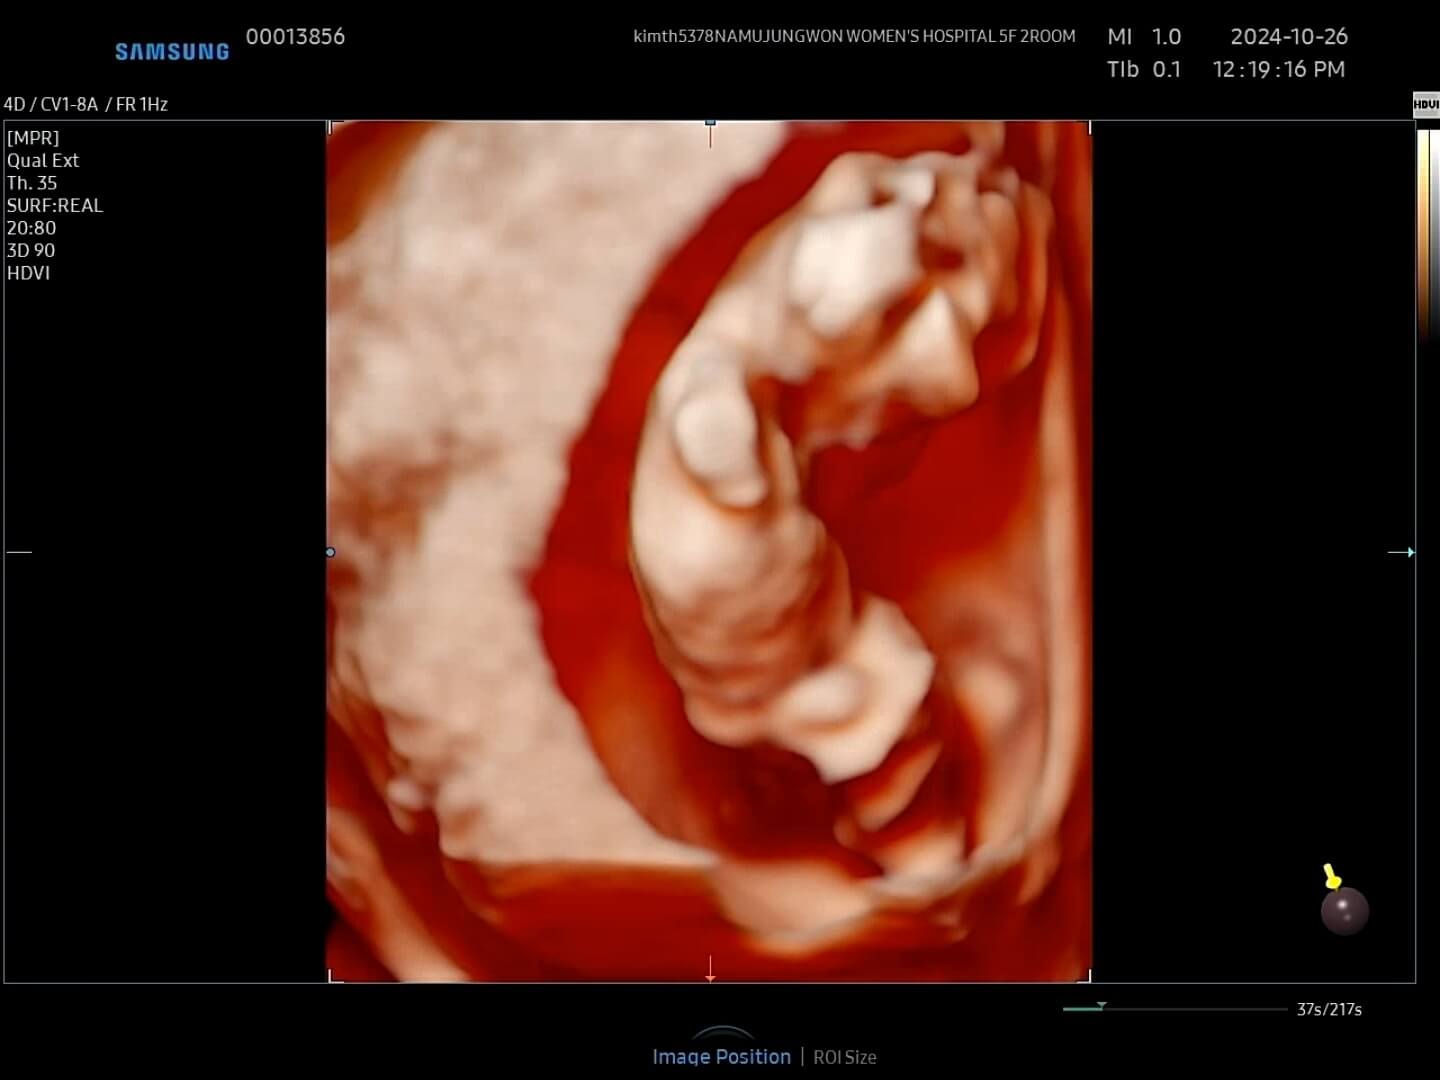

8주차-초음파사진 8주에서 9주 정도에는 초음파 사진을 보시면 아시겠지만, 손과 발이 나와서 마치 하리보 젤리의 젤리곰 같은 배아를 보실 수 있습니다. 거의 1~2주일만에 이렇게 큰 모습을 보니까 너무너무 귀여웠습니다. 2주만에 본 꾸미는 젤리곰이 되어서 꿈틀꿈틀 춤을 추고 있었고, 마치 짧고 귀여운 팔로 '엄마, 안녕!' 하는 기분이었어요.

12주-입체초음파 12주에는 첫 입체초음파를 보게 되면서 팔, 다리가 잘 형성되었는지 정도를 보는 것 같아요. 12주부터 '태아'라고 부르기도 한답니다. 우리 꾸미는 처음에는 등을 돌리고 있다가 서서히 얼굴을 보여줬습니다. 벌써부터 귀여워요! 아들인지 딸인지 너무 궁금했는데요, 성별은 입체 초음파가 아닌 일반 초음파로 봐야한다고 하셨어요.